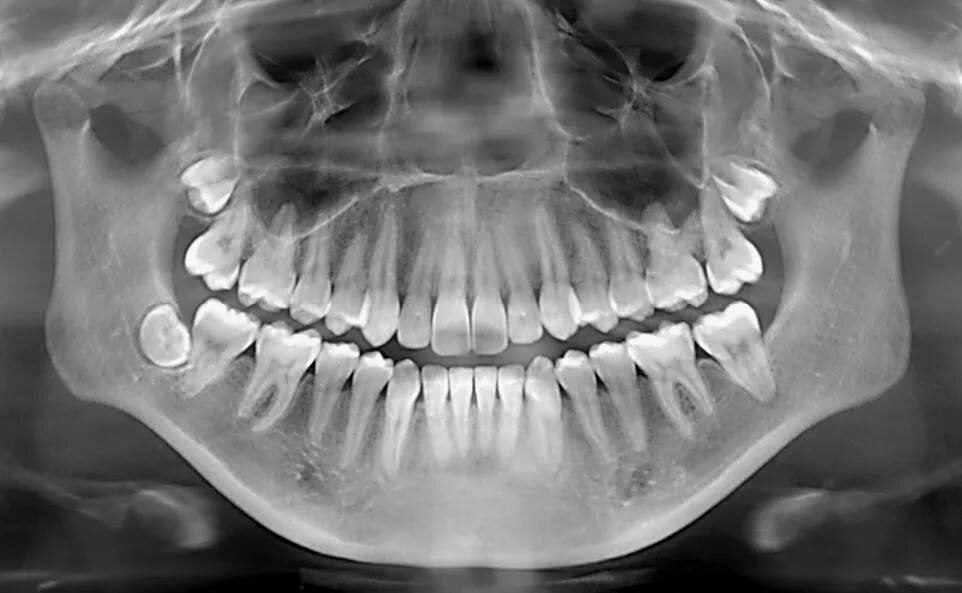

Фото: kvb.by, фото может носить иллюстрационный характер, КТ зубов в Витебске: Расширяя Горизонты Стоматологической Диагностики

В мире современной стоматологии точность диагностики – это не просто желательный бонус, а абсолютная необходимость. От нее зависит не только выбор правильного метода лечения, но и его эффективность, предсказуемость результата и, конечно же, комфорт пациента. Одним из наиболее мощных инструментов, позволяющих стоматологам Витебска заглянуть внутрь зуба и окружающей костной ткани с беспрецедентной детализацией, является компьютерная томография (КТ) зубов. Эта технология произвела настоящую революцию, переведя диагностику на качественно новый уровень.